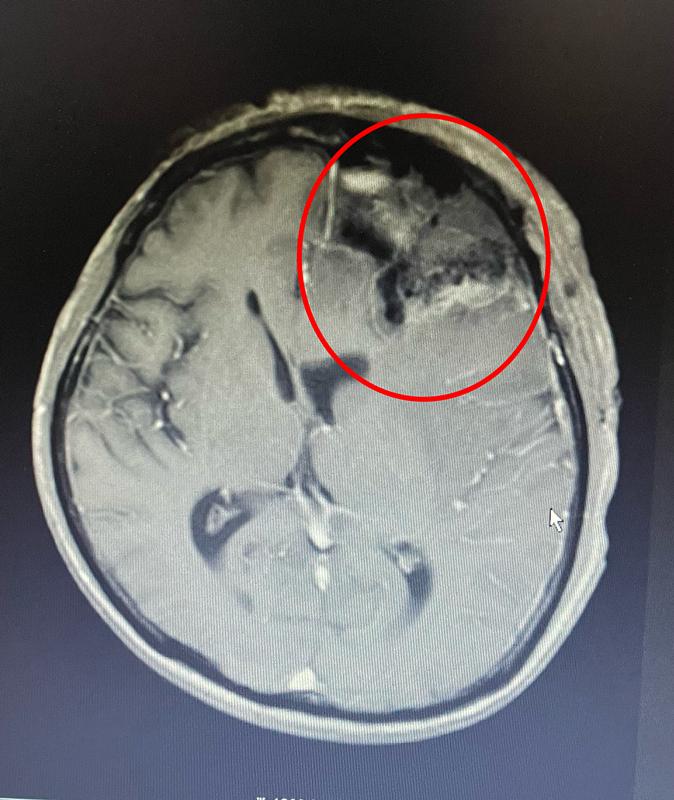

手术顺利完成,患者术后第一天神志恢复清醒,能正常对答,四肢肢体活动良好,术后病理为黑色素瘤。

患者手术前后头颅核磁共振

术后两周,患者康复出院,返回当地医院进行后续治疗。经过为期半年的跟踪随访,覃爷爷的语言功能与反应能力均恢复良好,且无新发神经功能障碍。